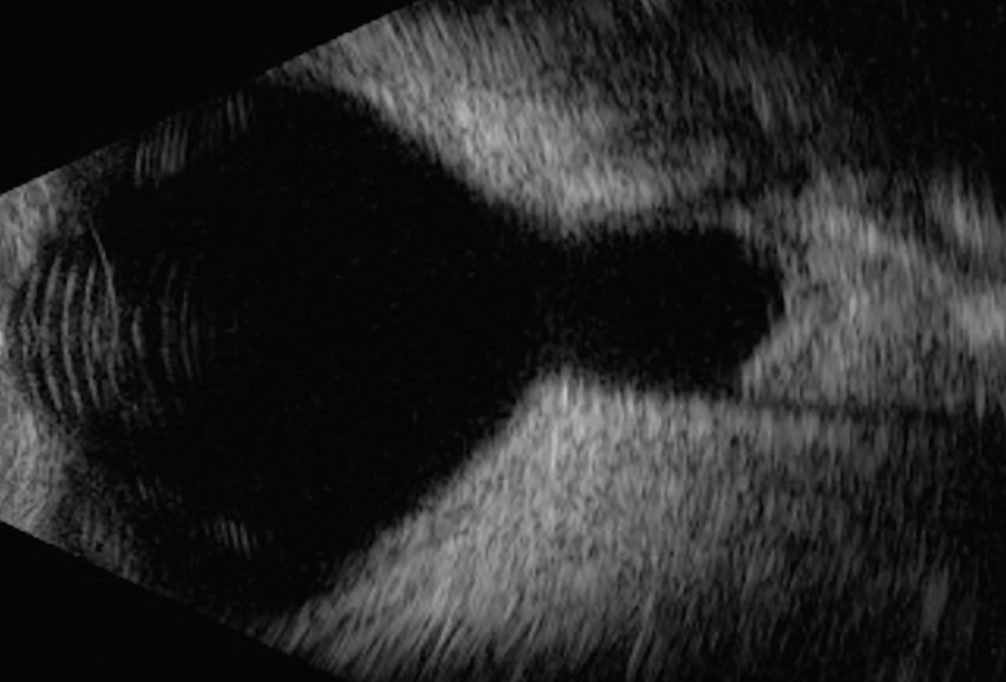

Intraoperative B scan ultrasonography revealed a large peripapillary staphyloma with cyst (Figure 3).

Figure 3. B scan ultrasonography of the left eye demonstrating a large peripapillary staphyloma with cyst. |